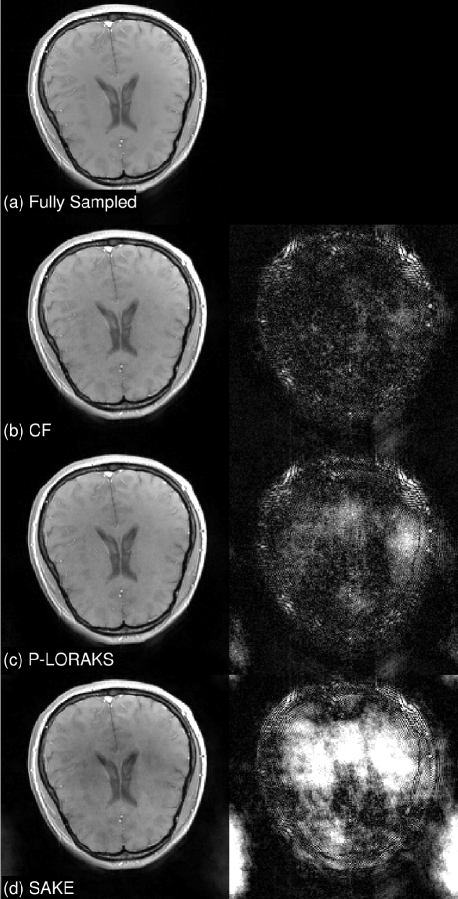

For 2D, we retrospectively downsampled three 3T brain datasets using three different acceleration rates, R and and four different sampling patterns: (i) 2D random; (ii) 2D random + ACS region; (iii) 2D random + ACS region; (iv) 1D random + ACS readout lines. The data were compressed to eight virtual coils. Quantitative results and representative frames are in Table 1 and Figure 1, respectively. Not surprisingly, the performances of CF and SAKE* are similar because they essentially solve the same 2D problem, but CF converges in fewer iterations and has a significantly smaller memory footprint.